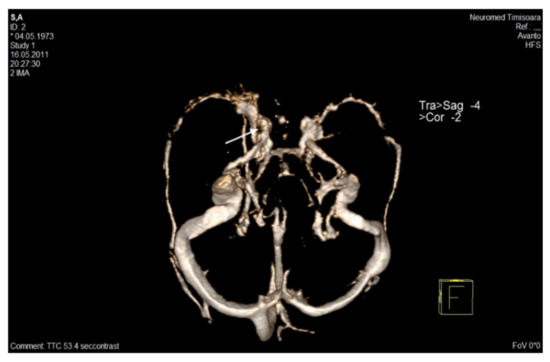

MRV can detect the thrombus and can assess the spontaneous recanalization or recanalization following therapy. Total recanalization is not mandatory for symptomatic recovery, and the presence of collateral pathways may also be identified in MRV [95,96]. (Table 2) (Figure 5) [81].

Figure 5.

CE–MRA, venous time—VRT reconstruction in the axial plane: lacunar image in right cavernous sinus (arrow). CE–MRA: Contrast-enhanced–magnetic resonance angiography; VRT: Volume rendering technique [81].